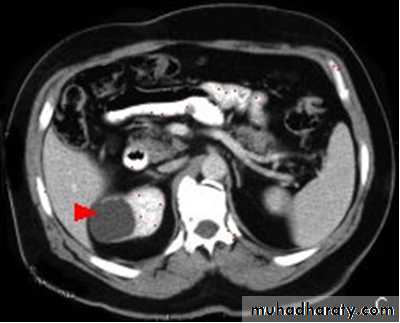

Renal cell carcinomas

Spherical and often lobulated, usually isodense to renal parenchyma.Focal necrotic areas may result in areas of low density, and stippled calcification may be present in the interior of the mass.

Renal cell carcinomas enhance, but not to the same degree as the normal renal parenchyma. The enhancement is inhomogeneous.

Check LN, liver, adrenal, pancreas, bone, renal vein and IVC